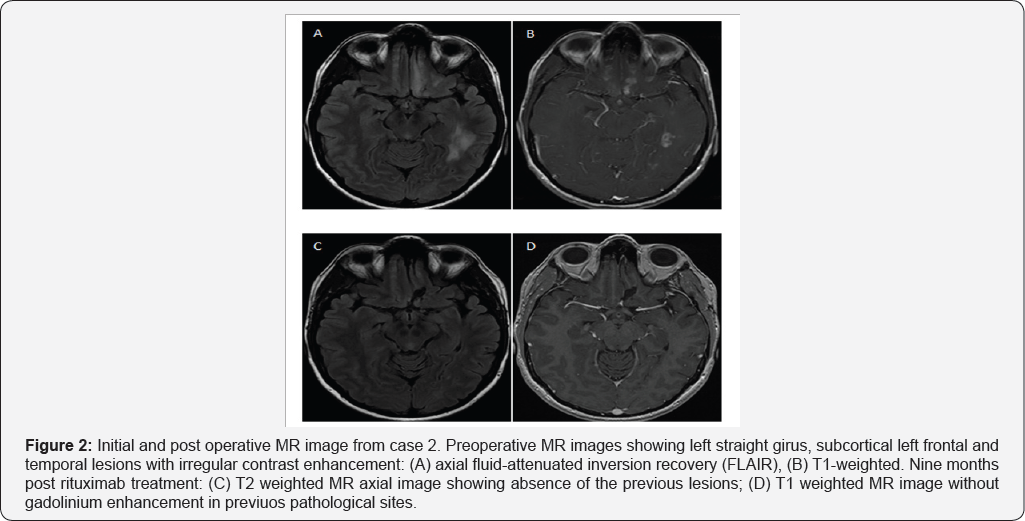

A 29 year old woman without any significant past medical history had several complex partial seizures. Her post ictal neurological examination was normal. MRI revealed multiple hyperintense lesions with contrast-enhanced T1-weighted heterogeneous pattern in left temporal and frontal lobes (Figure 2). Single and multi-voxel spectroscopy showed elevated Cho. Blood laboratory tests were normal including thyroid profile,HIV, HCV, HBV, VDRL, ANCA C, ANCA P, Toxoplasmosis IgG and IgM, and Brucellosis IgG and IgM. Cerebrospinal fluid (CSF) was normal, PCR for enterovirus, tuberculosis, and VDRL were all negative. With a presumption of brain tumor, a left fronto-basal lesion biopsy was performed through a supraorbital lateral approach. A grayish lesion with minimal bleeding was observed.

Pathological examination reported moderate perivascular lymphocytic infiltration and reactive gliosis; 3-20 CD markers were not representative. PCR tested in brain tissue for VZV, HSV- 1-2-6-8, JCV, VEB, citomegalovirus (CMV) were all negative.Congo red stain was negative. These findings were consistent with a diagnosis of PACNS. The patient was first treated with high-dose of intravenous methylprednisolone for five days and then continued with oral prednisone lmg/kg/day for six months and posterior tappering. Fourteen months after diagnosis she had increased seizure frequency associated with a new left temporal lobe lesion. She received rituximab, 2gr total doses by infusions of lgr separated by 14 day. After 9 months of rituximab treatment, she had good outcome, with seizure and lesion remission (Figure 2).